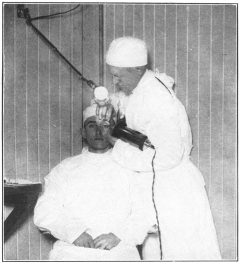

X-Raying the Teeth and Jaw—Health Often Depends on Their Good Condition | 224 |

Throat Examination—Important in Determining Physical Condition | 225 |